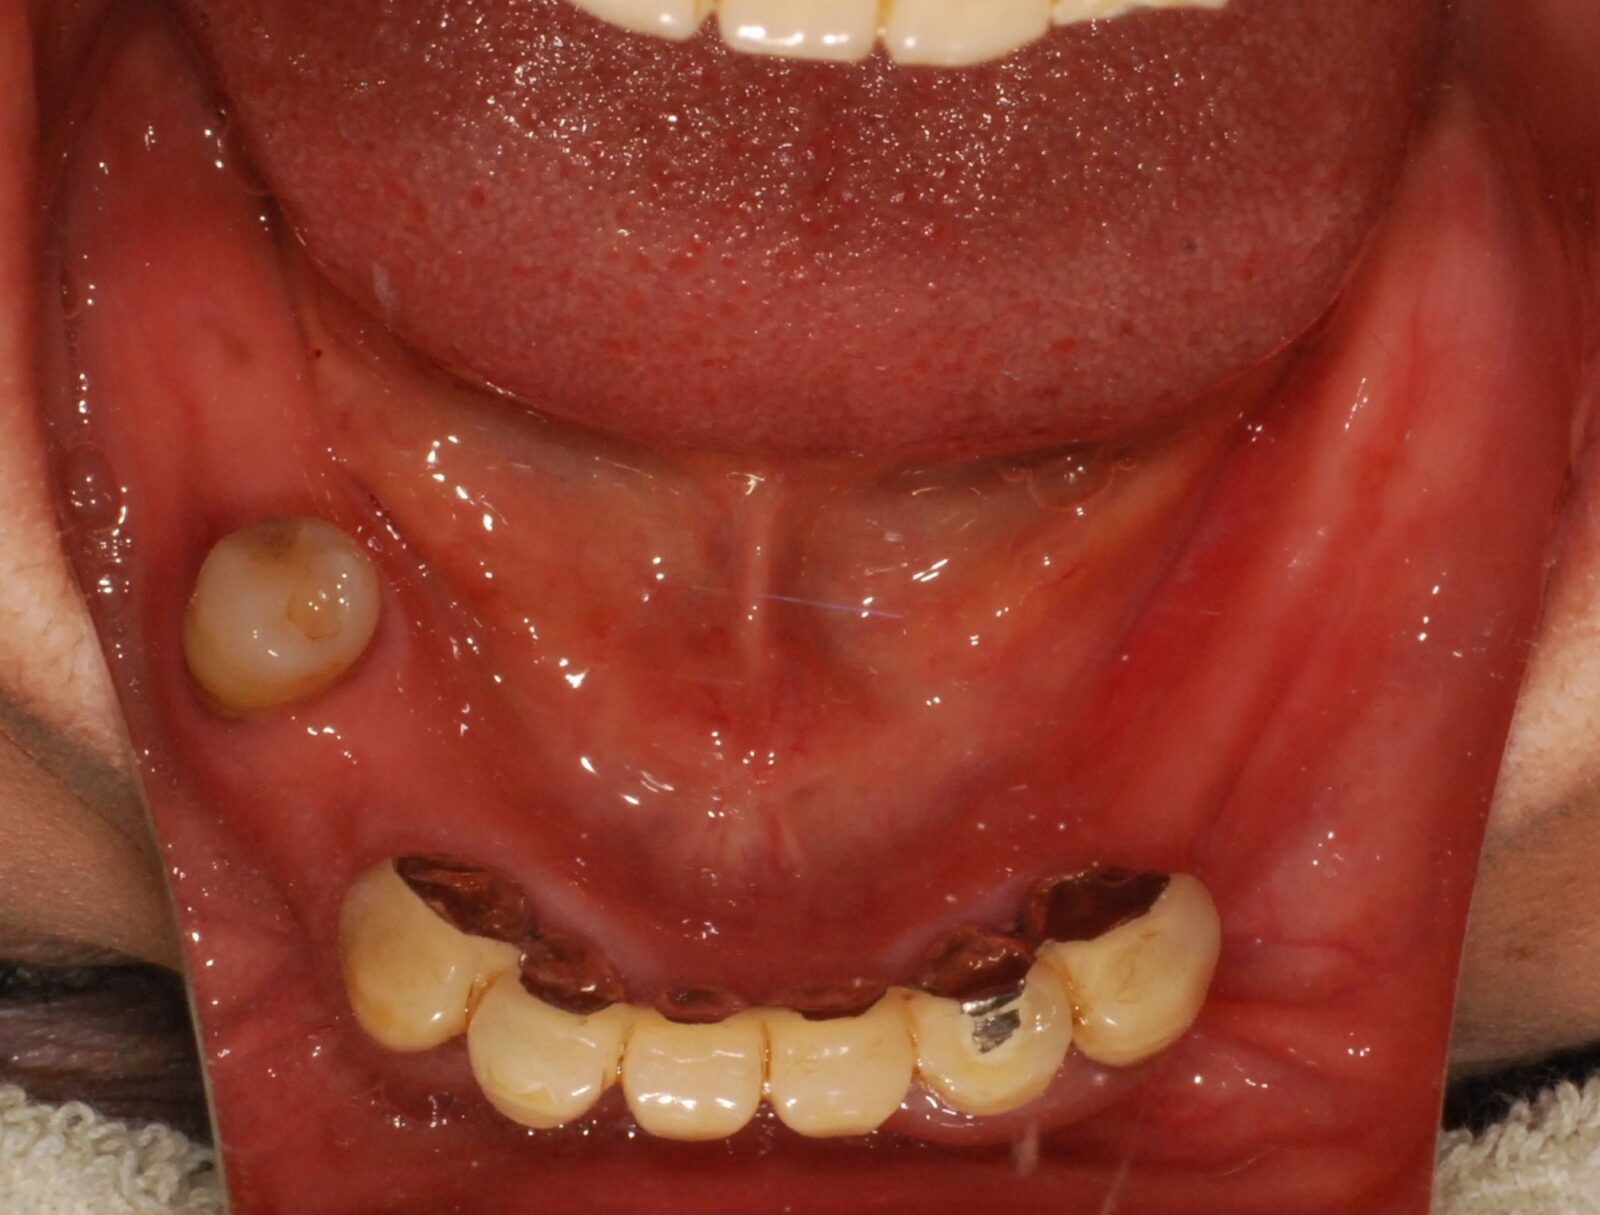

次の写真は、当院で製作した磁性アタッチメント義歯の症例です。

上の写真が、初診時のお口の状態です。

上顎には1本しか歯が残っていませんでしたが、その部分に磁石を取り付けました。総入れ歯にも磁石を取り付け、磁力で入れ歯を固定させました。

下顎にも歯が入っていますが、こちらはインプラント治療で対応しました。